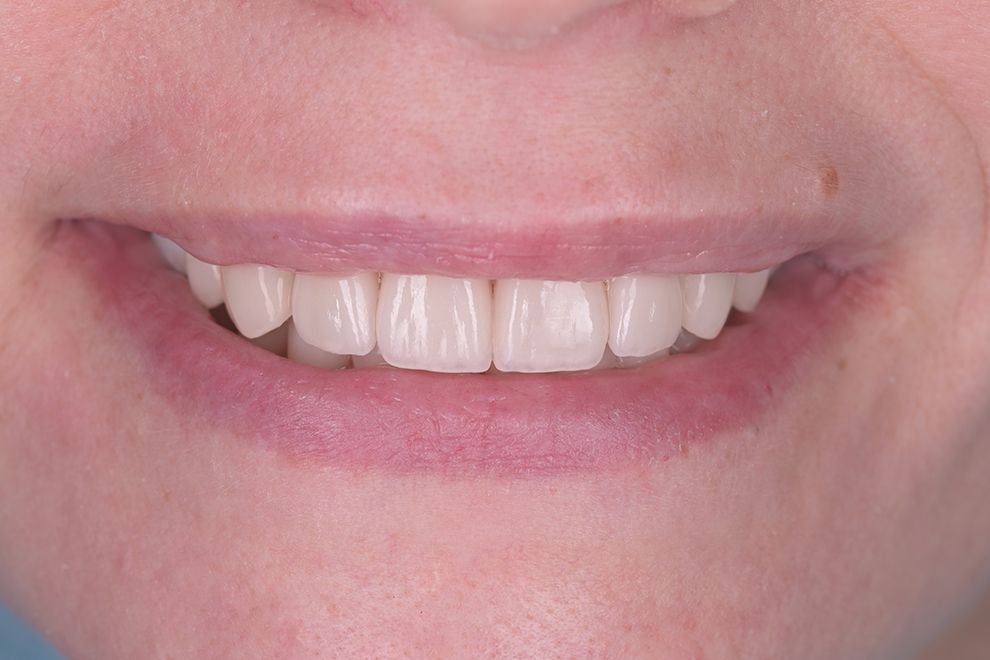

до и после

Хочу выразить огромную благодарность доктору Котоменкову Сергею Юрьевичу, превосходный доктор, уделяющий внимание деталям, профессионал своего дела. " С Вашей помощью, я восстановила не только свою улыбку , но и вновь обрела уверенность в себе. Оказывается посещение стоматолога ничуть не хуже визита к психологу. Идеально восстановил зону улыбки, сейчас и зубы свои не узнать, я в восторге. Спасибо за Ваш профессионализм и заботу. Однозначно рекомендую этого потрясающего доктора, тем кто хочет видеть здоровые и красивые зубы на все 1000%. Так же хочу сказать спасибо огромное прекрасному доктору хирургу-имплантологу Кушнаревой Анне Анатольевне за удаление 8-ого зуба, все прошло выше всех похвал, на следующий день и забыла что удалили зуб. И конечно ребятам ассистентам за их труд и внимательное отношение к пациенту.